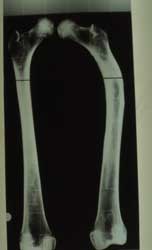

Fémur

Le fémur droit présente une angulation de sa partie supérieure qui signe une fracture de l’enfance. Celle-ci a été parfaitement traitée par la méthode hippocratique, connue avant l’an mil par les médecins arabes.